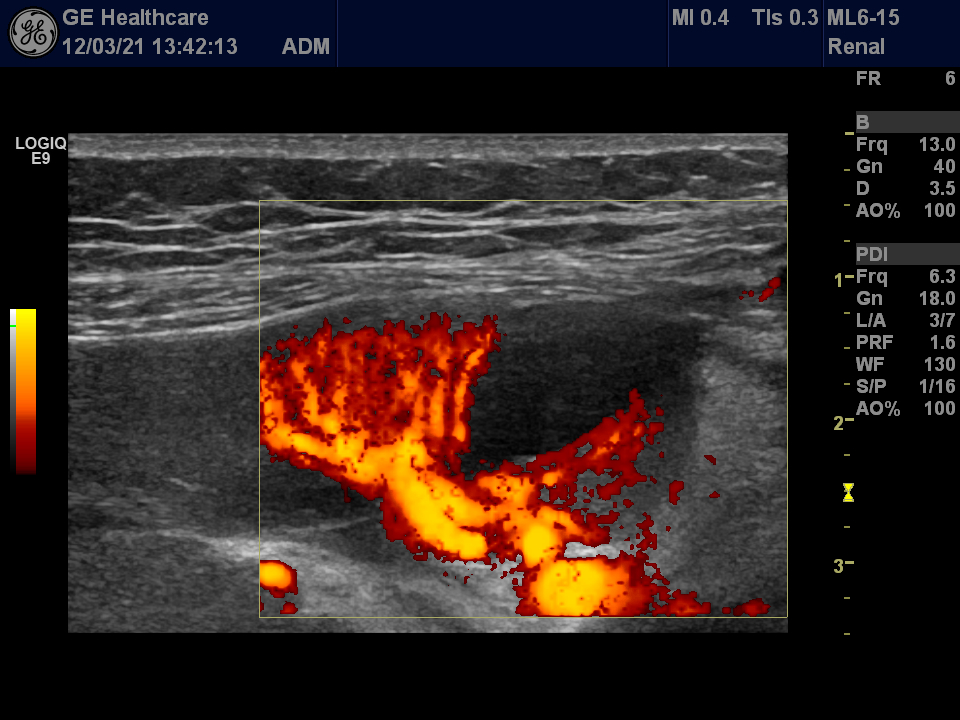

Small infarction of a transplanted kidney Szerző: admin | márc 22, 2012 | CEUS, Renal infarction | Nincsenek hozzászólások wedge shaped hypoechoic area in the transplanted kidney lack of circulation acceleration decreased in the surrounding arteries segmental artery show normal Doppler waveform no vascularisation at all – infarction